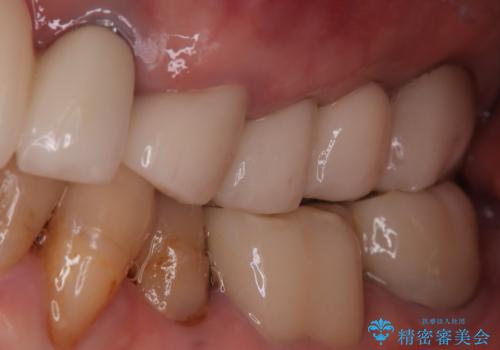

歯の破折 食べる喜びが蘇るインプラント治療